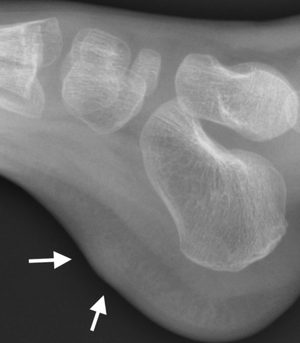

![]() | |

| X-ray foot: Fibrous hamartoma of infancy | |